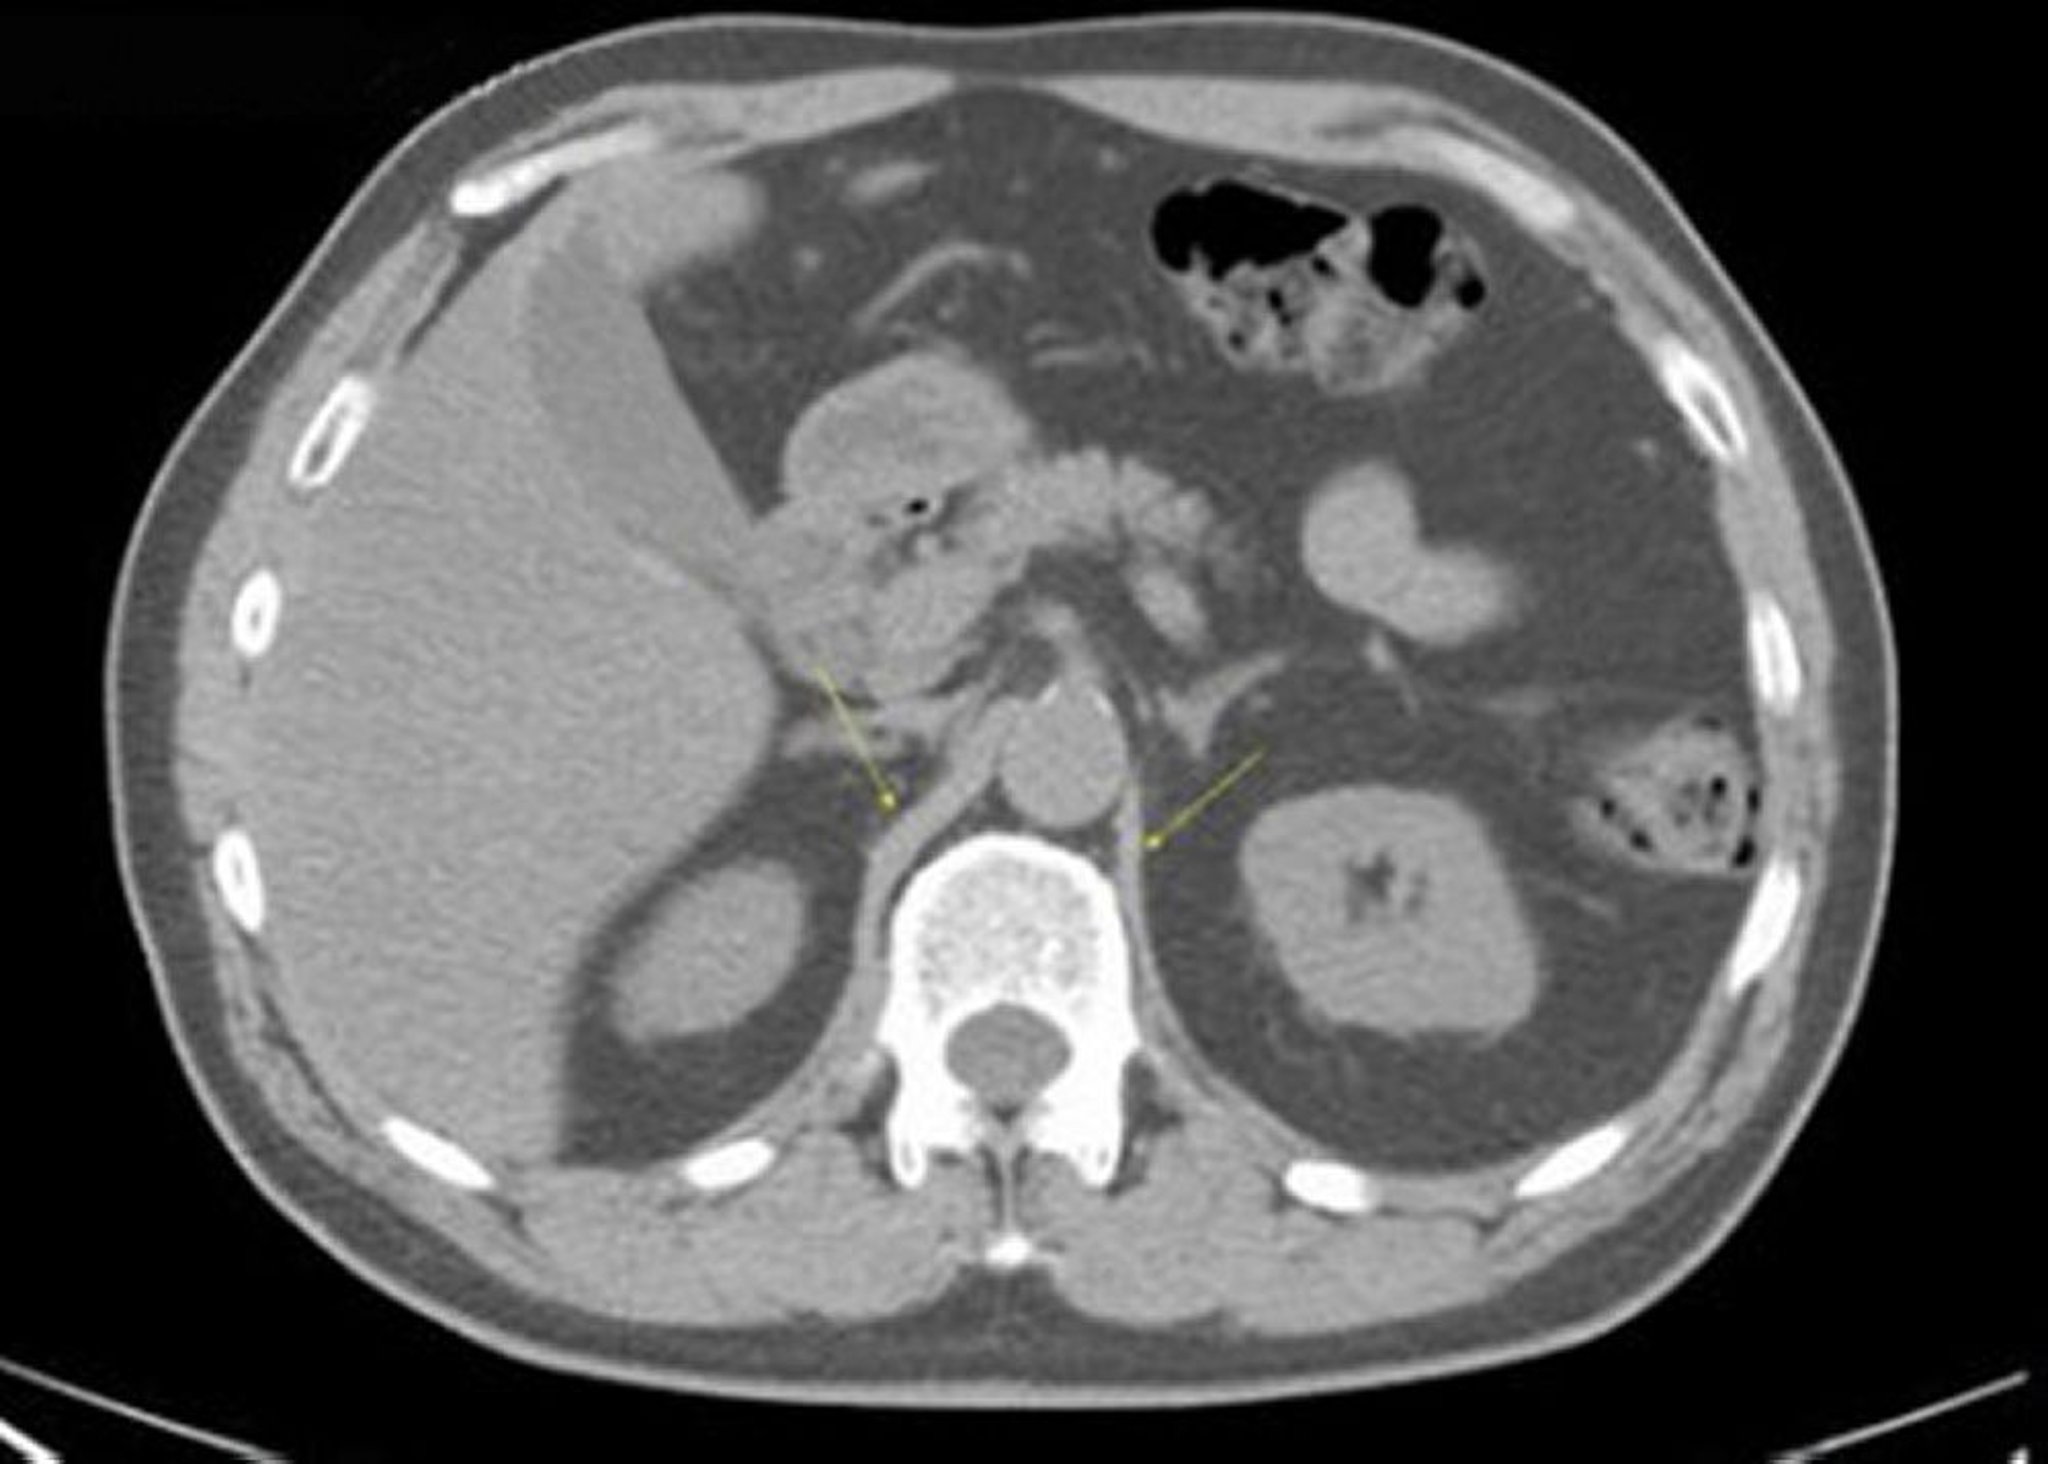

TC senza contrasto dell'addome e della pelvi che mostra un'anatomia normale (Slide 10)

Questa immagine mostra le crura (pilastri) del diaframma (frecce).